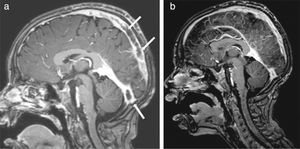

The patient had normal blood pressure; however, bilateral papilledema was detected. Magnetic resonance imaging (MRI) showed hyperintense thrombosis in the superior sagittal sinus and in both proximal segments of transverse sinuses (Fig. 1a). Subcutaneous low-molecular-weight heparin (LMWH) was started. The patient was investigated for a prothrombotic state and a methylenetetrahydrofolate reductase (MTHFR) heterozygous mutation was found. Azathioprine was added. One month later bilateral papilledema was detected again. The brain MRI was repeated and a new thrombosis distal to the superior sagittal sinus was detected. After permission from the ministry of health, infliximab was used at a 5mg/kg/day dose and 3 doses were applied on the 0, 2 and 6 weeks. Before the infliximab, azathioprine was stopped; prednisolone was tapered and stopped at the 7th day of infliximab. Ten days after first dose of infliximab, C-reactive protein was decreased to normal range, and both frequency and severity of the oral aphthous lesions were reduced. Resolution of the thrombosis was seen after the second dose of infliximab in the brain MRI (Fig. 1b). Ongoing therapies consist of colchicine and LMWH. Infliximab was well tolerated by this patient; no drug-induced side effects were recorded.

(a) Magnetic resonance imaging of brain before the infliximab. Hyperintense thrombosis filling the superior sagittal sinus and proximal segments of both transverse sinuses was showed and (b) after second dose of infliximab, significant dissolution of the thrombosis was observed in the brain MRI.

Vascular lesions in BD can involve both arterial and venous vessels, and cause refractory complications with poor prognosis. In our patient, cerebral thrombosis was refractory to treatment which corticosteroids, immunosuppressants, and anti-coagulants. The administration of infliximab resulted in the improvement of clinical and laboratory findings. In addition, cerebral sinus thrombosis in MRI was reduced.